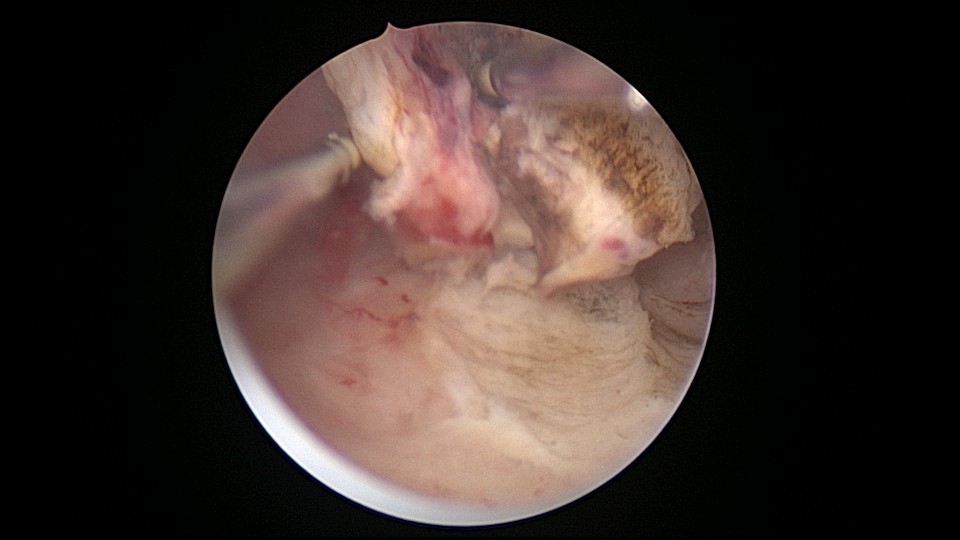

患者25岁,G1P0,停经52天,稽留流产,B超宫内偏右查见大小约2.4cmx1.0cmx1.7cm孕囊回声,形态规则,内可见直径约0.4cm的卵黄囊回声,未见胎芽,孕囊旁肌层最薄处厚约0.5cm,子宫中下段回声连续性欠佳,似可见一分隔回声。2021年7月宫腔镜探查,胚胎着床于宫腔前壁偏右,宫颈内口及宫腔左侧壁粘连。清除妊娠组织,单极电针分粘,恢复宫腔形态,双侧输卵管开口显露(第一次怀孕,宫腔粘连原因?)。2022年7月自然妊娠,2023年3月足月剖宫产分娩。2024年12月,外院人流术后1+月,宫内残留,与后壁肌层分界欠清,局部血流信号增多,到我院宫腔镜切除残留组织(后3张图片)。现患者30岁,G3P1。宫腔粘连常常不能阻止妊娠,但胚胎停育发生率增加。